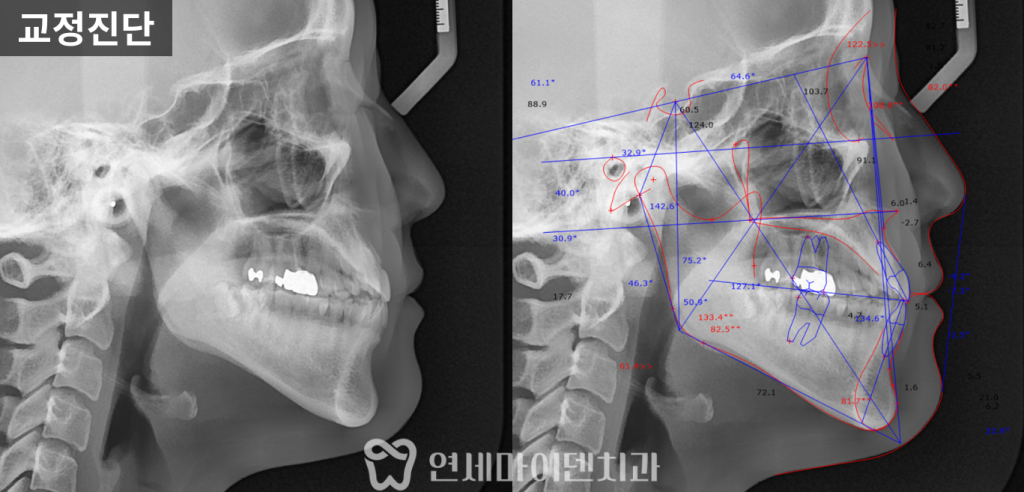

옆모습 방사선 사진으로 시행한 정밀 교정진단 결과,

아래턱이 위턱보다 더 발달한 골격적 3급 부정교합 상태였습니다.

이런 경우 외관에서 아래턱이 앞으로 나와보이는

주걱턱 형태를 띄게 됩니다.

특히 치아교정 전 상악과 하악 사진에서

맞지 않는 교합을 보상하기 위해 아래 앞니가 안쪽으로 많이 쓰러진 것을 확인했습니다.

여러가지 방면으로 교정과 전문의가 직접 교정진단 후에

좁은 악궁을 넓히고 중심선을 회복하며 아래턱도 들어가야하는 치료 계획이 필요했습니다.